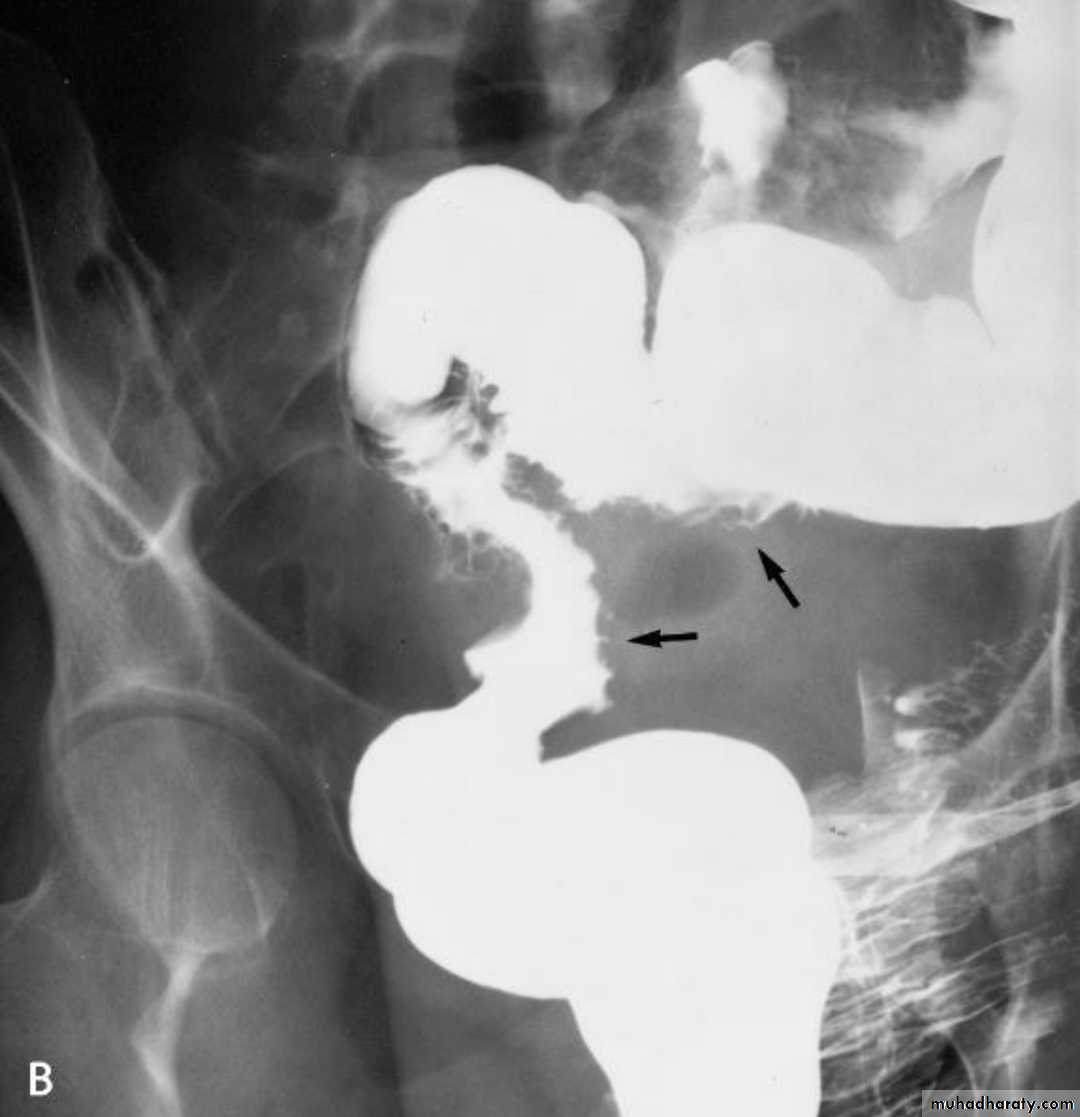

Barium enema 3 presentation

1. infiltrative ( Apple core sign ) lesion infiltrate bowel wall from outside

2.ill defined filling defect within the lumen of the bowel

3.could be ulcerative nodule or ulcerative lesion .